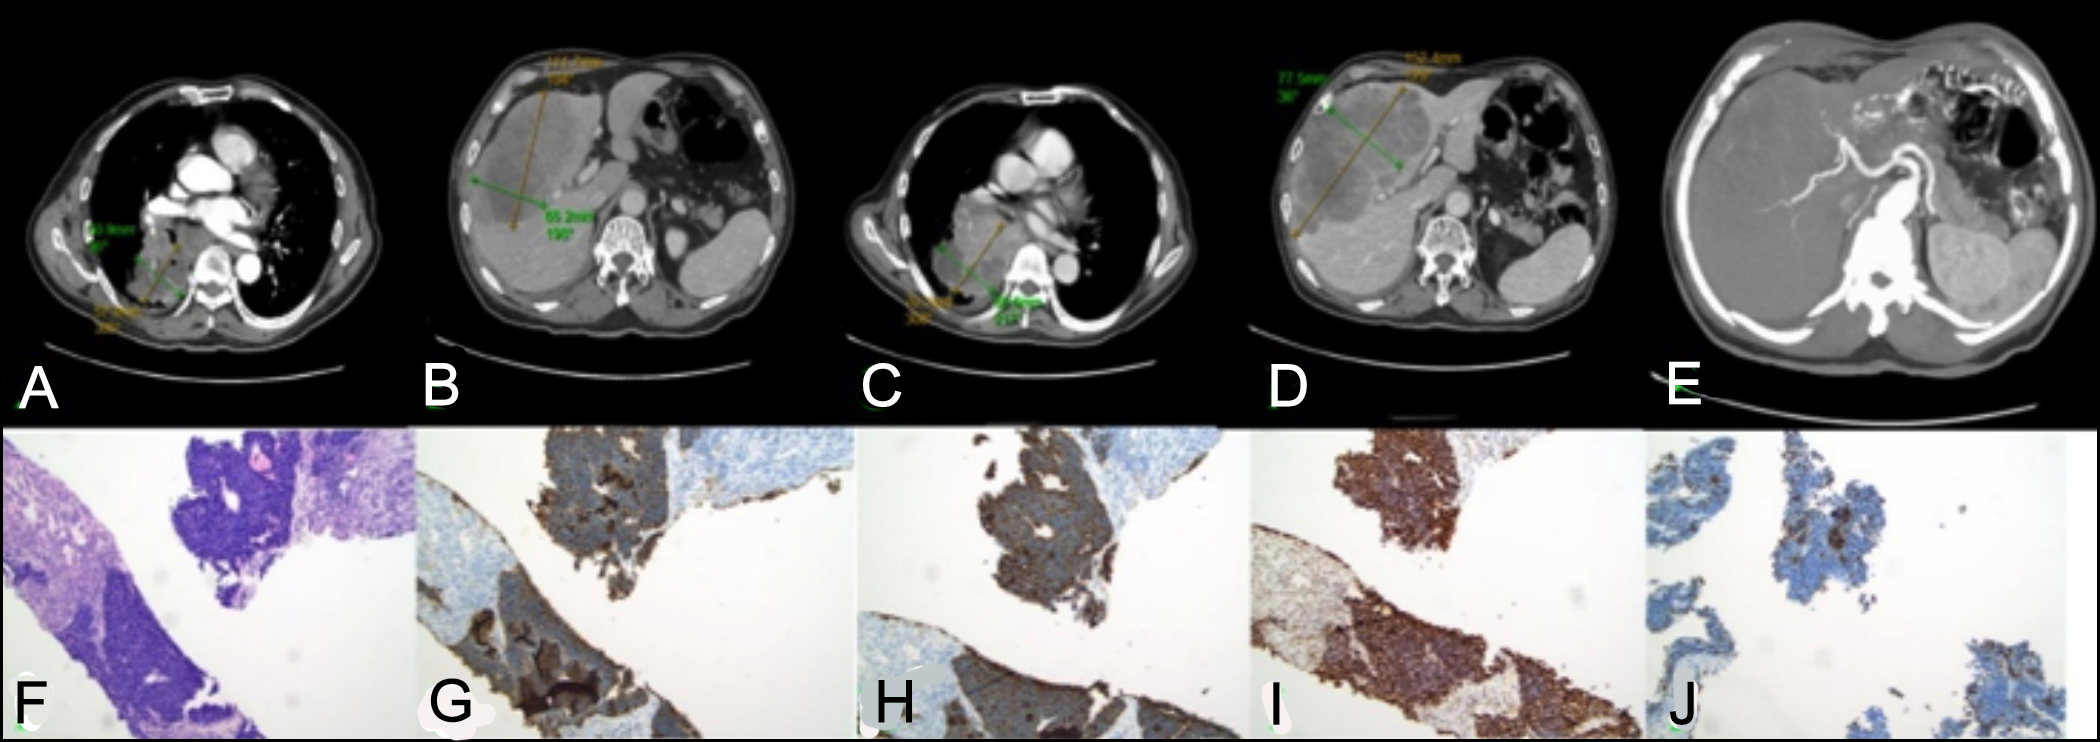

A male patient was admitted on May 26, 2024, with persistent cough. The CT scan revealed tumours in the right lung and liver (Figure 1A, B). Pathologic and immunohistochemical analysis of lung tissue suggested lung adenocarcinoma, supporting a preliminary diagnosis of lung adenocarcinoma with hepatic metastases. Notably, serum neuron-specific enolase (NSE) was significantly elevated (>740.00 ng/mL; normal: <16.50 ng/mL). Following a gastroenterology consultation, a CT-guided liver biopsy was performed on July 1, demonstrating the following profile: P-CK (-), CK7 (-), TTF-1 (-), Napsin A (-), P40 (-), CK5/6 (-), P63 (-), SMARCA4 (+), CD56 (+), chromogranin A (CgA) (+), synaptophysin (Syn) (+), Ki-67 (+, about 20%) (Figure 1F-J). When the CT scan and gastrointestinal endoscopy ruled out extrahepatic NETs, a comprehensive analysis of imaging, pathology, and clinical features ultimately confirmed grade 3 (G3) PHNETs. To reconfirm the result, Ga-68 DOTATATE scan was recommended; however, the patient declined the examination due to financial constraints. On July 11, the patient initiated two cycles of chemotherapy and immunotherapy (etoposide 140 mg, carboplatin 0.4 g, toripalimab 200 mg, and octreotide acetate microspheres 20 mg). The follow-up CT on September 14 reported disease progression (Figure 1C and D). Transarterial chemoembolisation was deferred due to declining haemoglobin (78 g/L). Unfortunately, the patient passed away two months later.

Figure 1: (A, B) Chest and abdominal contrast-enhanced CT on May 26, 2024, showing an approximately 5.7 × 5.1 cm mass in the right lung lobe (arterial phase) and an approximately 11.2 × 6.6 cm mass in the liver (portal phase). (C, D) Follow-up CT on September 14, 2024, demonstrating enlargement of both tumours. (E) Maximum intensity projection (MIP) indicating hepatic arterial supply to the hepatic mass. (F) Histopathological microscopy showing abnormal cellular proliferation. (G-J) Immunohistochemical results demonstrating positive staining for CgA, Syn, SMARCA4, with a Ki-67 ratio of approximately 20%.